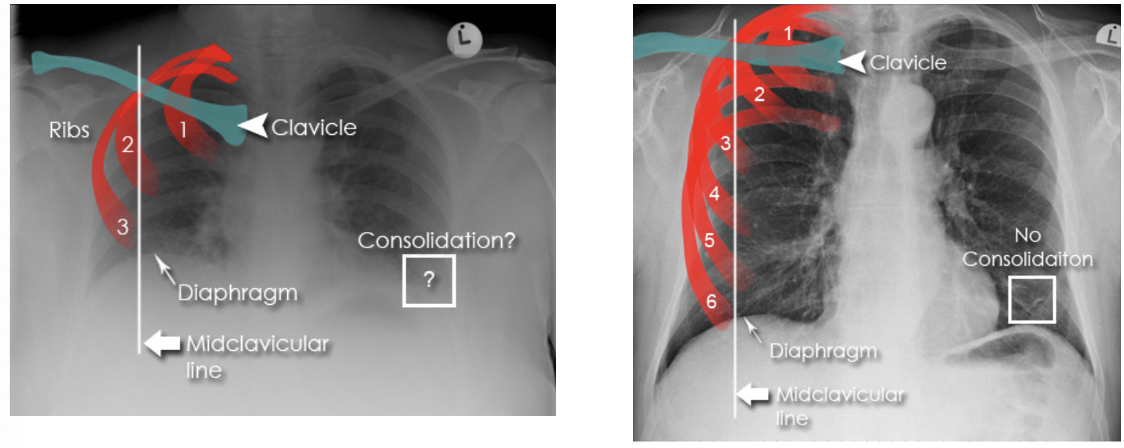

How can you tell if a CXR has been taken during a good inspiration?

Count the anterior ribs on the right → 6 anterior ribs should be visible above the right hemidiaphragm

Anteriorly, which rib should intersect the diaphragm and where?

6th rib at the mid-clavicular level

How can you assess for hyperexpansion on a CXR?

1. Count ribs → >7th anterior rib intersecting the diaphragm at the mid-clavicular line

2. Check for flattening of hemidiaphragms